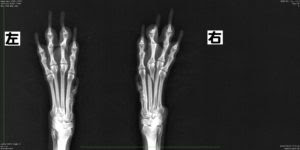

犬 骨折 レントゲン費用- ピンニングとは、骨の中心に金属のピンを入れて固定する手術です。 金属のピンは、レントゲンで骨の中心に棒状に白く映ります。 手術から2週間後です。 骨が細くなってきました。 手術から2ヶ月後です。 2本ある骨のうちの1本は消えて無くなっています。 ピンニングで手術した骨は癒合しましたが骨密度の低下が見られます。 その10日後に、同じ場所 犬の捻挫の診断には レントゲンが有効 なことが多いです。 下のレントゲン写真をご覧いただくと、右側が正常で、左側は捻挫をしています。 左側は、膝の側副靭帯が切れているため、骨の隙間が広くなっています。

症例紹介 小型犬の全中手骨骨折 ギプス固定による治療 さくら動物病院